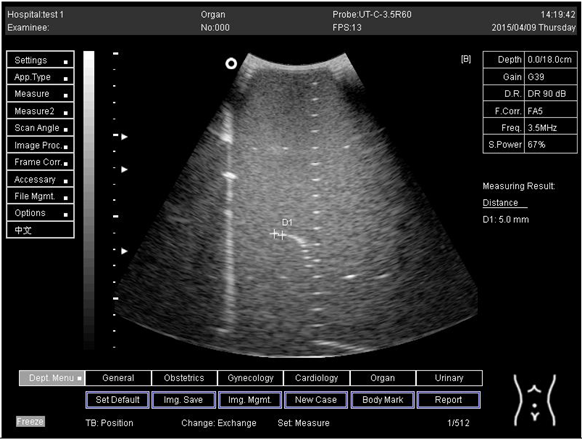

18.0Axial resolution

Biomimetics 07 00130 i027

D1 = 5.0

D2 = 4.1

D3 = 3.1

Lateral resolution

Biomimetics 07 00130 i028